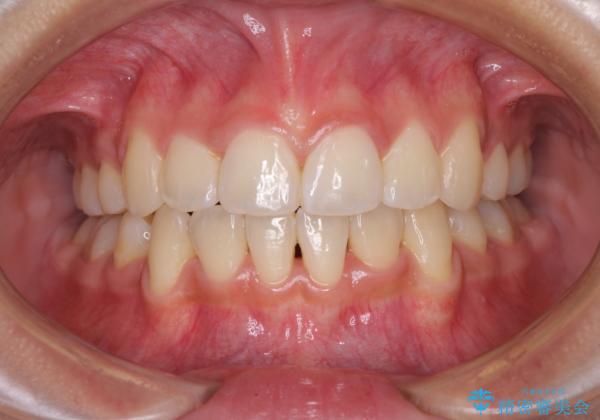

- 上下前歯のデコボコと、それによる磨きづらさを気にして来院された患者様です。

叢生解消のため、上下左右第一小臼歯4本を抜歯し、ワイヤー装置にて矯正治療を行うこととしました。

半年ほどで前歯のデコボコは改善され、汚れの溜まりやすさは解消されました。

抜歯スペースを閉じるために期間がかかりましたが、当初予定通り2年強で終えることができました。